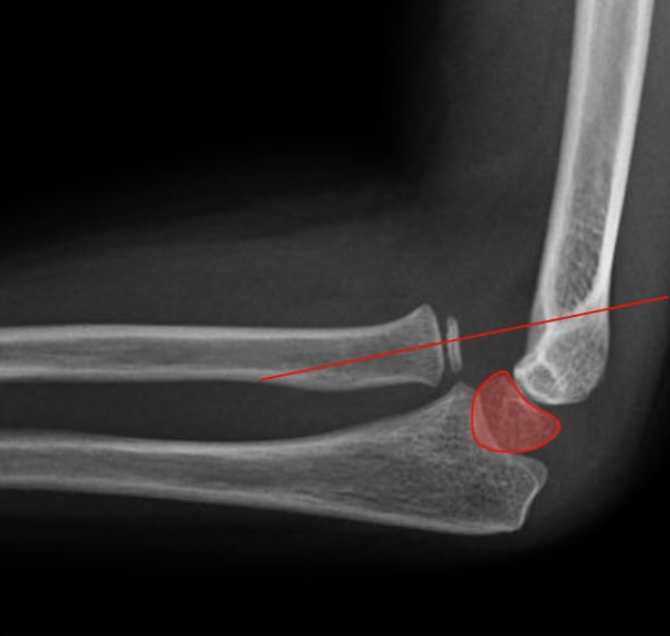

Luxación + fractura de cúpula radial: en estos casos se encuentra dislocado el codo y asociado una fractura de la cabeza de radio; debe primero reducir la luxación para determinar el tipo de tratamiento que se puede dar a la cúpula radial.

ANTES: Luxofractura codo derecho: - en emergencia se reduce, se hacen diagnósticos y planificamos cirugía.

DESPUÉS: Luxofractura de codo post cirugía y en rehabilitación, con adecuados movimientos en flexoextensión y pronosupinación.